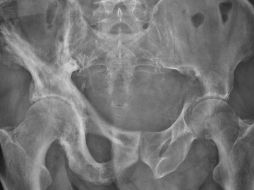

Jalisco Afectan lesiones de cadera a ocho de cada 10 adultos mayores 7 de marzo de 2010 - 15:58 hs Salud Tercera edad